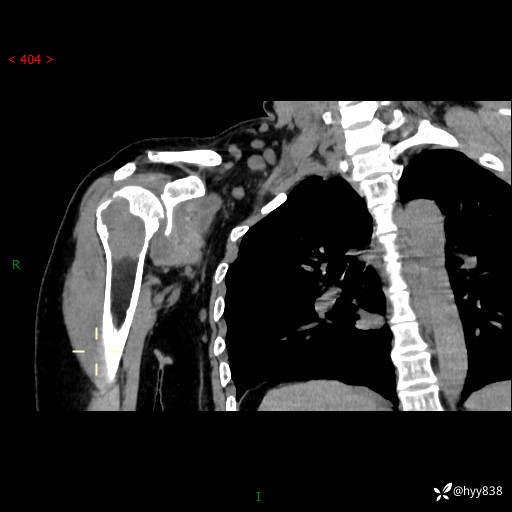

中年女性,发现右肩关节占位2天。有特征、有细节---结果公布~

年龄:47岁

主诉:发现右肩关节占位2天

现病史:患者3年前摔伤致右肩部疼痛,未行特殊处理,后右肩活动时轻度疼痛,患者未引起重视。1月前上述症状加重,于当地县人民医院就诊,2023-07-10右肩关节MR:右肱骨头、肩胛骨及周围软组织异常信号。现患者右肩可触及质硬包块,活动时疼痛,无头晕头痛、恶心呕吐、腹痛腹胀等,为求进一步治疗,来我科就诊,门诊以“右股骨占位性病变”收入我科。 起病以来,患者精神、饮食、睡眠可,大小便正常,体力、体重未见明显变化。

右肩关节CT平扫